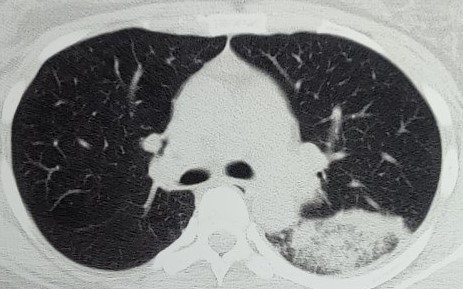

CT - CHEST

Large non homogenous opacities with air bronchogram and surrounding ground glass opacities is seen in the superior segment of the left lower lobeLIGHTS CRITERIA